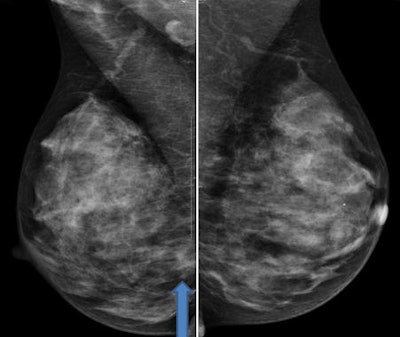

![]() |

| Cancer in the posterior right breast on digital mammography. All images courtesy of Maxine Jochelson, MD. |